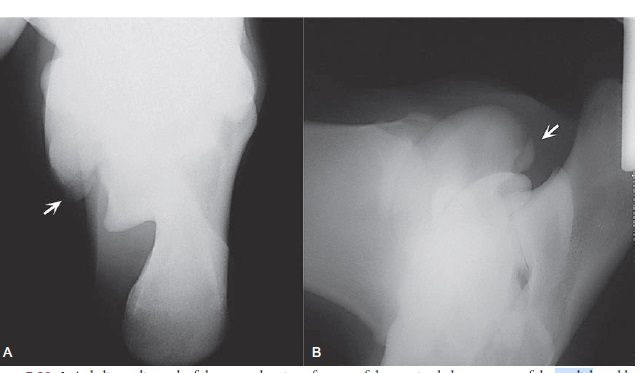

An extensive chronic fracture of the proximal plantar aspect of the medial trochlear ridge (MTR)

Fracture of the tarsus causes and regions

*Traumatic

External impact

1. Tibial malleoli

2. Trochlea rridges

3. Tubercalcaneus

4. Fourth tarsal bone

Rotatory twisting

1. Talu body

2. Distal tibia

3. Luxations

Extensive fractures of the proximal plantar aspect ofthe MTR have significant synovial and joint capsuleattachment (Figure 34.7). Dissection of the soft tissuesmay require arthroscopic scissors, curved fixed‐bladescalpels, periosteal elevators, and synovial resectors. Removal of the free fracture fragmentmay require forceps with aggressive teeth, includinginsertion of Ochsner forceps or towel clamps.Rarely, large fractures will need to be divided using anosteotome, prior to removal in pieces.